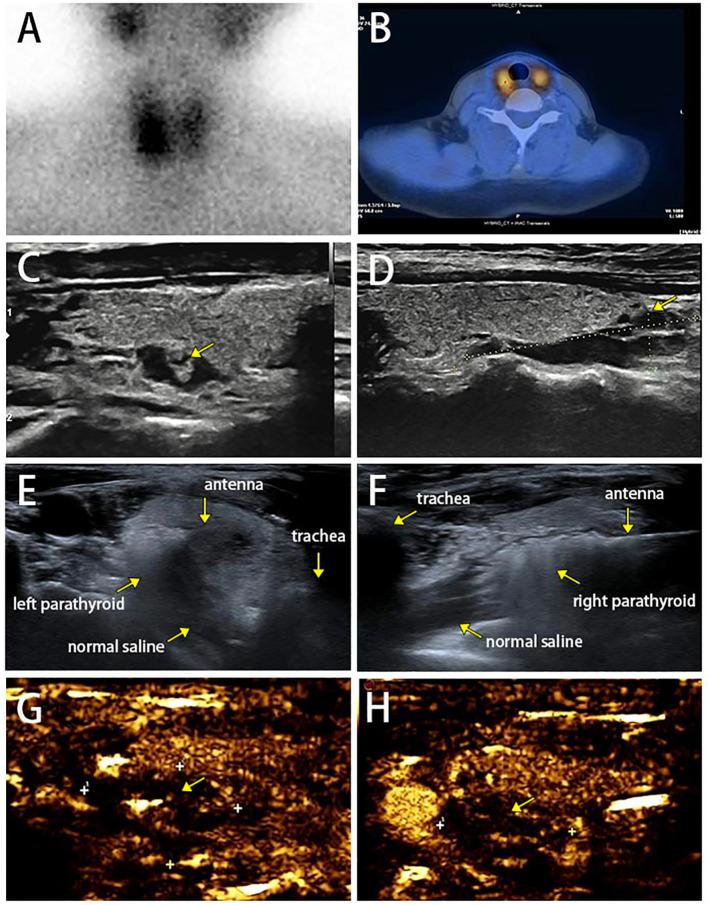

We reported a 44-year-old woman with MEN1 combined with PHPT who was diagnosed through genetic screening of the patient and her family members. After parathyroidectomy to remove one parathyroid gland, the patient suffered from persistent high levels of serum calcium and parathyroid hormone, which returned to normal at up to 8 months after ultrasound-guided microwave ablation (MWA) for bilateral parathyroid glands, suggesting an acceptable short-term prognosis.

我们报告了一例 44 岁的 MEN1 合并 PHPT 女性患者,该患者通过对患者及其家庭成员进行基因筛查而确诊。甲状旁腺切除术后切除了一个甲状旁腺,患者的血清钙和甲状旁腺激素持续升高,在双侧甲状旁腺超声引导微波消融(MWA)后长达 8 个月才恢复正常,提示短期预后尚可。